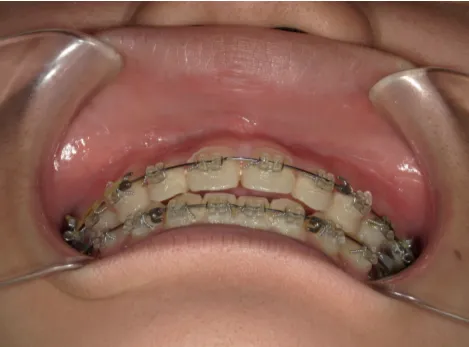

治療中⑧高1:15y11m 抜歯治療中

治療中⑨高2:17y1m 抜歯治療中

治療後⑩高2:17y7m 抜歯治療終了